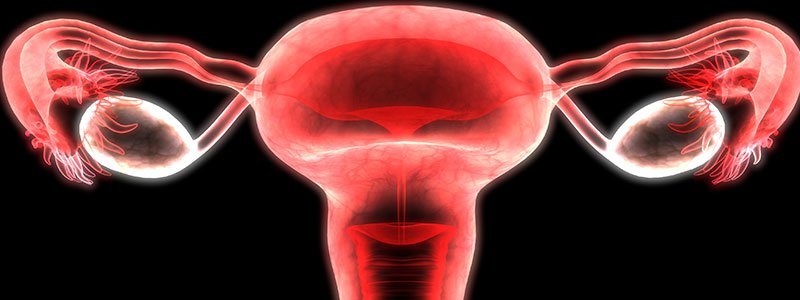

A:Fibroids (also called leiomyomas or myomas) are a type of muscular tumors that grows within the uterus (womb), in the uterine wall, or on the outside surface of the uterus.

Women may develop a single uterine fibroid, or there may be many. Fibroids can vary widely in size and can be so small they are invisible to the naked eye or even as large as a grapefruit or bigger.

A:If fibroids are suspected, a doctor will usually start with a history asking about your symptoms. They can often feel fibroids during a pelvic exam.

Imaging tests may also be ordered to check for the presence of fibroids, including: